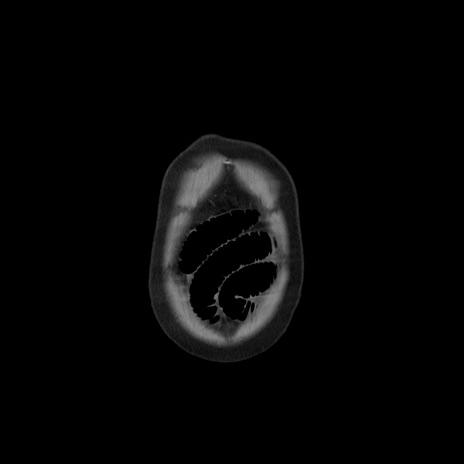

矢状断像